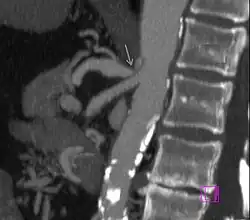

|

Further evaluation and confirmation can be obtained via angiography to investigate the anatomy of the celiac artery.[5] Historically, conventional angiography was used, although this has been largely replaced by less invasive techniques such as computed tomography (CT) and magnetic resonance (MR) angiography.[2][5] Because it provides better visualization of intra-abdominal structures, CT angiography is preferred to MR angiography in this setting.[5] The findings of focal narrowing of the proximal celiac artery with poststenotic dilatation, indentation on the superior aspect of the celiac artery, and a hook-shaped contour of the celiac artery support a diagnosis of MALS.[2] These imaging features are exaggerated on expiration, even in normal asymptomatic individuals without the syndrome.[2]

Proximal celiac artery stenosis with poststenotic dilatation can be seen in other conditions affecting the celiac artery.[2] The hook-shaped contour of the celiac artery is characteristic of the anatomy in MALS and helps distinguish it from other causes of celiac artery stenosis such as atherosclerosis.[2] This hooked contour is not entirely specific for MALS however, given that 10–24% of normal asymptomatic individuals have this anatomy.[2]